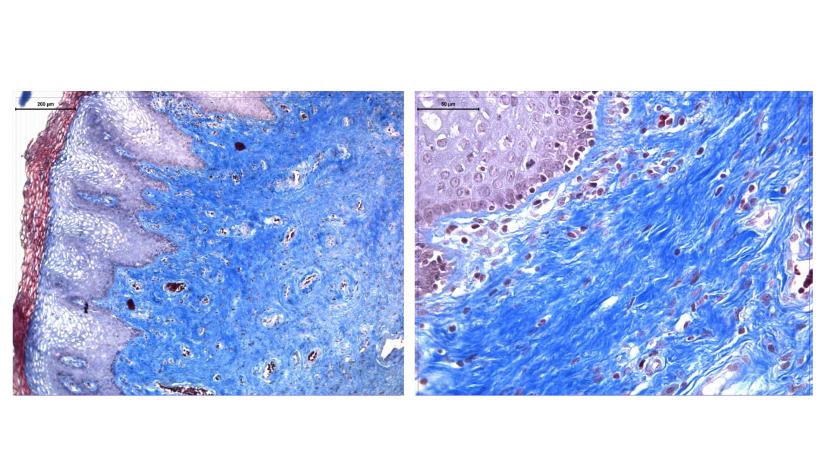

Fibröz madde ise üç tür lif içeriyor: kollagen lifler, elastik lifler ve retiküler lifler. Bu lifler dokunun dayanıklılığını ve esnekliğini sağlıyor.

Şekilde görüldüğü gibi fibroblast, makrofaj, yağ hücresi ve mast hücresi gibi farklı hücre türleri bu yapı içinde yer alıyor.

Amorf madde üç ana bileşenden oluşur: glikozaminoglikanlar, proteoglikanlar ve glikoproteinler. Bu maddeler jöle gibi bir yapı oluşturuyor.